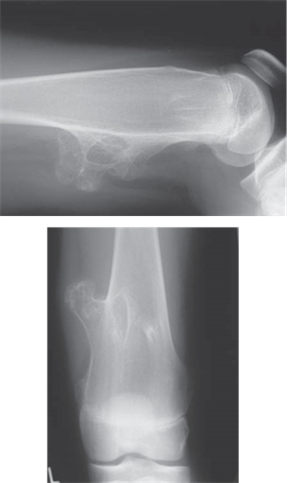

Describe what you see on these radiographs. What do you think is the most likely diagnosis?

When describing bone lesions remember: age; bone; site; matrix; margin; periosteal reaction; soft tissue mass; likely diagnoses.

The radiograph shows a lesion arising from the distal femoral metaphysis in a skeletally mature patient

The matrix of the lesion is mostly sclerotic, suggesting osteoblastic (bone-forming) activity; there are also a few small lytic (bone destruction) areas

The margins of the lesion are not clearly defined with a broad zone of transition into the surrounding bone

The cortex of the bone overlying the lesion is poorly defined and has been invaded by the lesion

The periosteum has been elevated anteriorly (Codmanโs triangle) and there is an associated โsunburstโ spiculation appearance

The lesion appears to have expanded out into the surrounding soft tissues

These features suggest that this is an aggressive, fast-growing, osteoblastic lesion of the distal femur โ the most likely diagnosis would be an osteosarcoma.